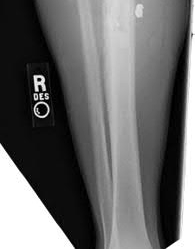

A 55-year-old female presents to the emergency room after falling off her balcony. She sustained the isolated, closed injury shown in Figures A and B. She is otherwise healthy, but routinely smokes 30 cigarettes per day. What would be the most appropriate sequence of treatment steps for definitive management of this injury?

Figures A and B show radiographs of a comminuted AO/OTA C3 fracture of the distal tibia. The most appropriate steps in the management of this patients injury would include: Closed reduction and splinting, external fixation, CT scan, and delayed open reduction internal fixation in this sequence.

Infection and wound healing problems are common with comminuted distal tibia fractures due to an increased incidence of soft-tissue complications associated with the operative management. Patients with a history of diabetes and smoking are at further risk. To decrease the risk of complications in this patient, a two-staged, delayed open reduction internal fixation technique is the best option for the treatment of severe pilon fractures.

Patterson et al. reviewed 23 consecutive patients with comminuted distal tibia fractures. They showed 0% infections or wound-healing problems in their patient population treated with a two-staged protocol. Their protocol involved fibula fixation with an intramedullary implant and application of a medial external fixator to to regain length and restore anatomic alignment. Re-evaluation of the limb occurred ten to fourteen days later for definitive fixation.

Sirkin et al. retrospectively reviewed 40 closed and 82 open pilon fractures (AO types 43A-C) that were treated with staged surgical management (avg. time from ext. fix. to formal reconstruction was 14 days (range 4 to 31) They reported 17% post-operative wound complication in the closed group and 11% post-operative wound complication in the open group (Gustilo Type I-III). They suggest the technique was successful in both closed and open pilon fractures.